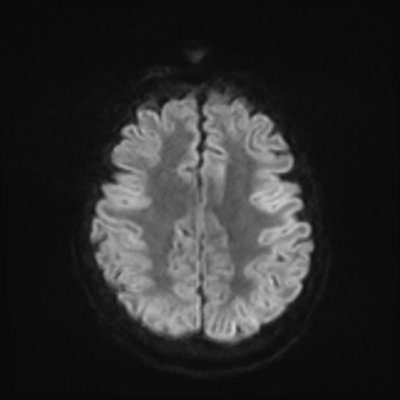

MRI brain (DWI)

You can clearly see diffuse cortical and basal ganglia diffusion restriction, and that of his deep cerebellar nuclei as well. The right occipital lobe abnormalities are a little more prominent, but then you remember that he is known to have had a right occipital stroke weeks ago.

In reviewing his data, you know that he doesn't have any of the strong predictors of a poor neurologic prognosis. However, based on these findings on MRI, along with the absent reactivity on cEEG, you are able to tell the primary team and the patient's family that he is likely to have a poor prognosis, based on these multiple moderate predictors. Recovery is not completely impossible-- there is more uncertainty with this prognostication than if we were able to get SSEPs-- but you're very worried about his outlook and that any potential recovery would require a very protracted rehabilitation period. Given his high cervical cord injury level, tracheostomy would be required anyway. So, it comes down to whether his family thinks he'd want to pursue these aggressive measures.